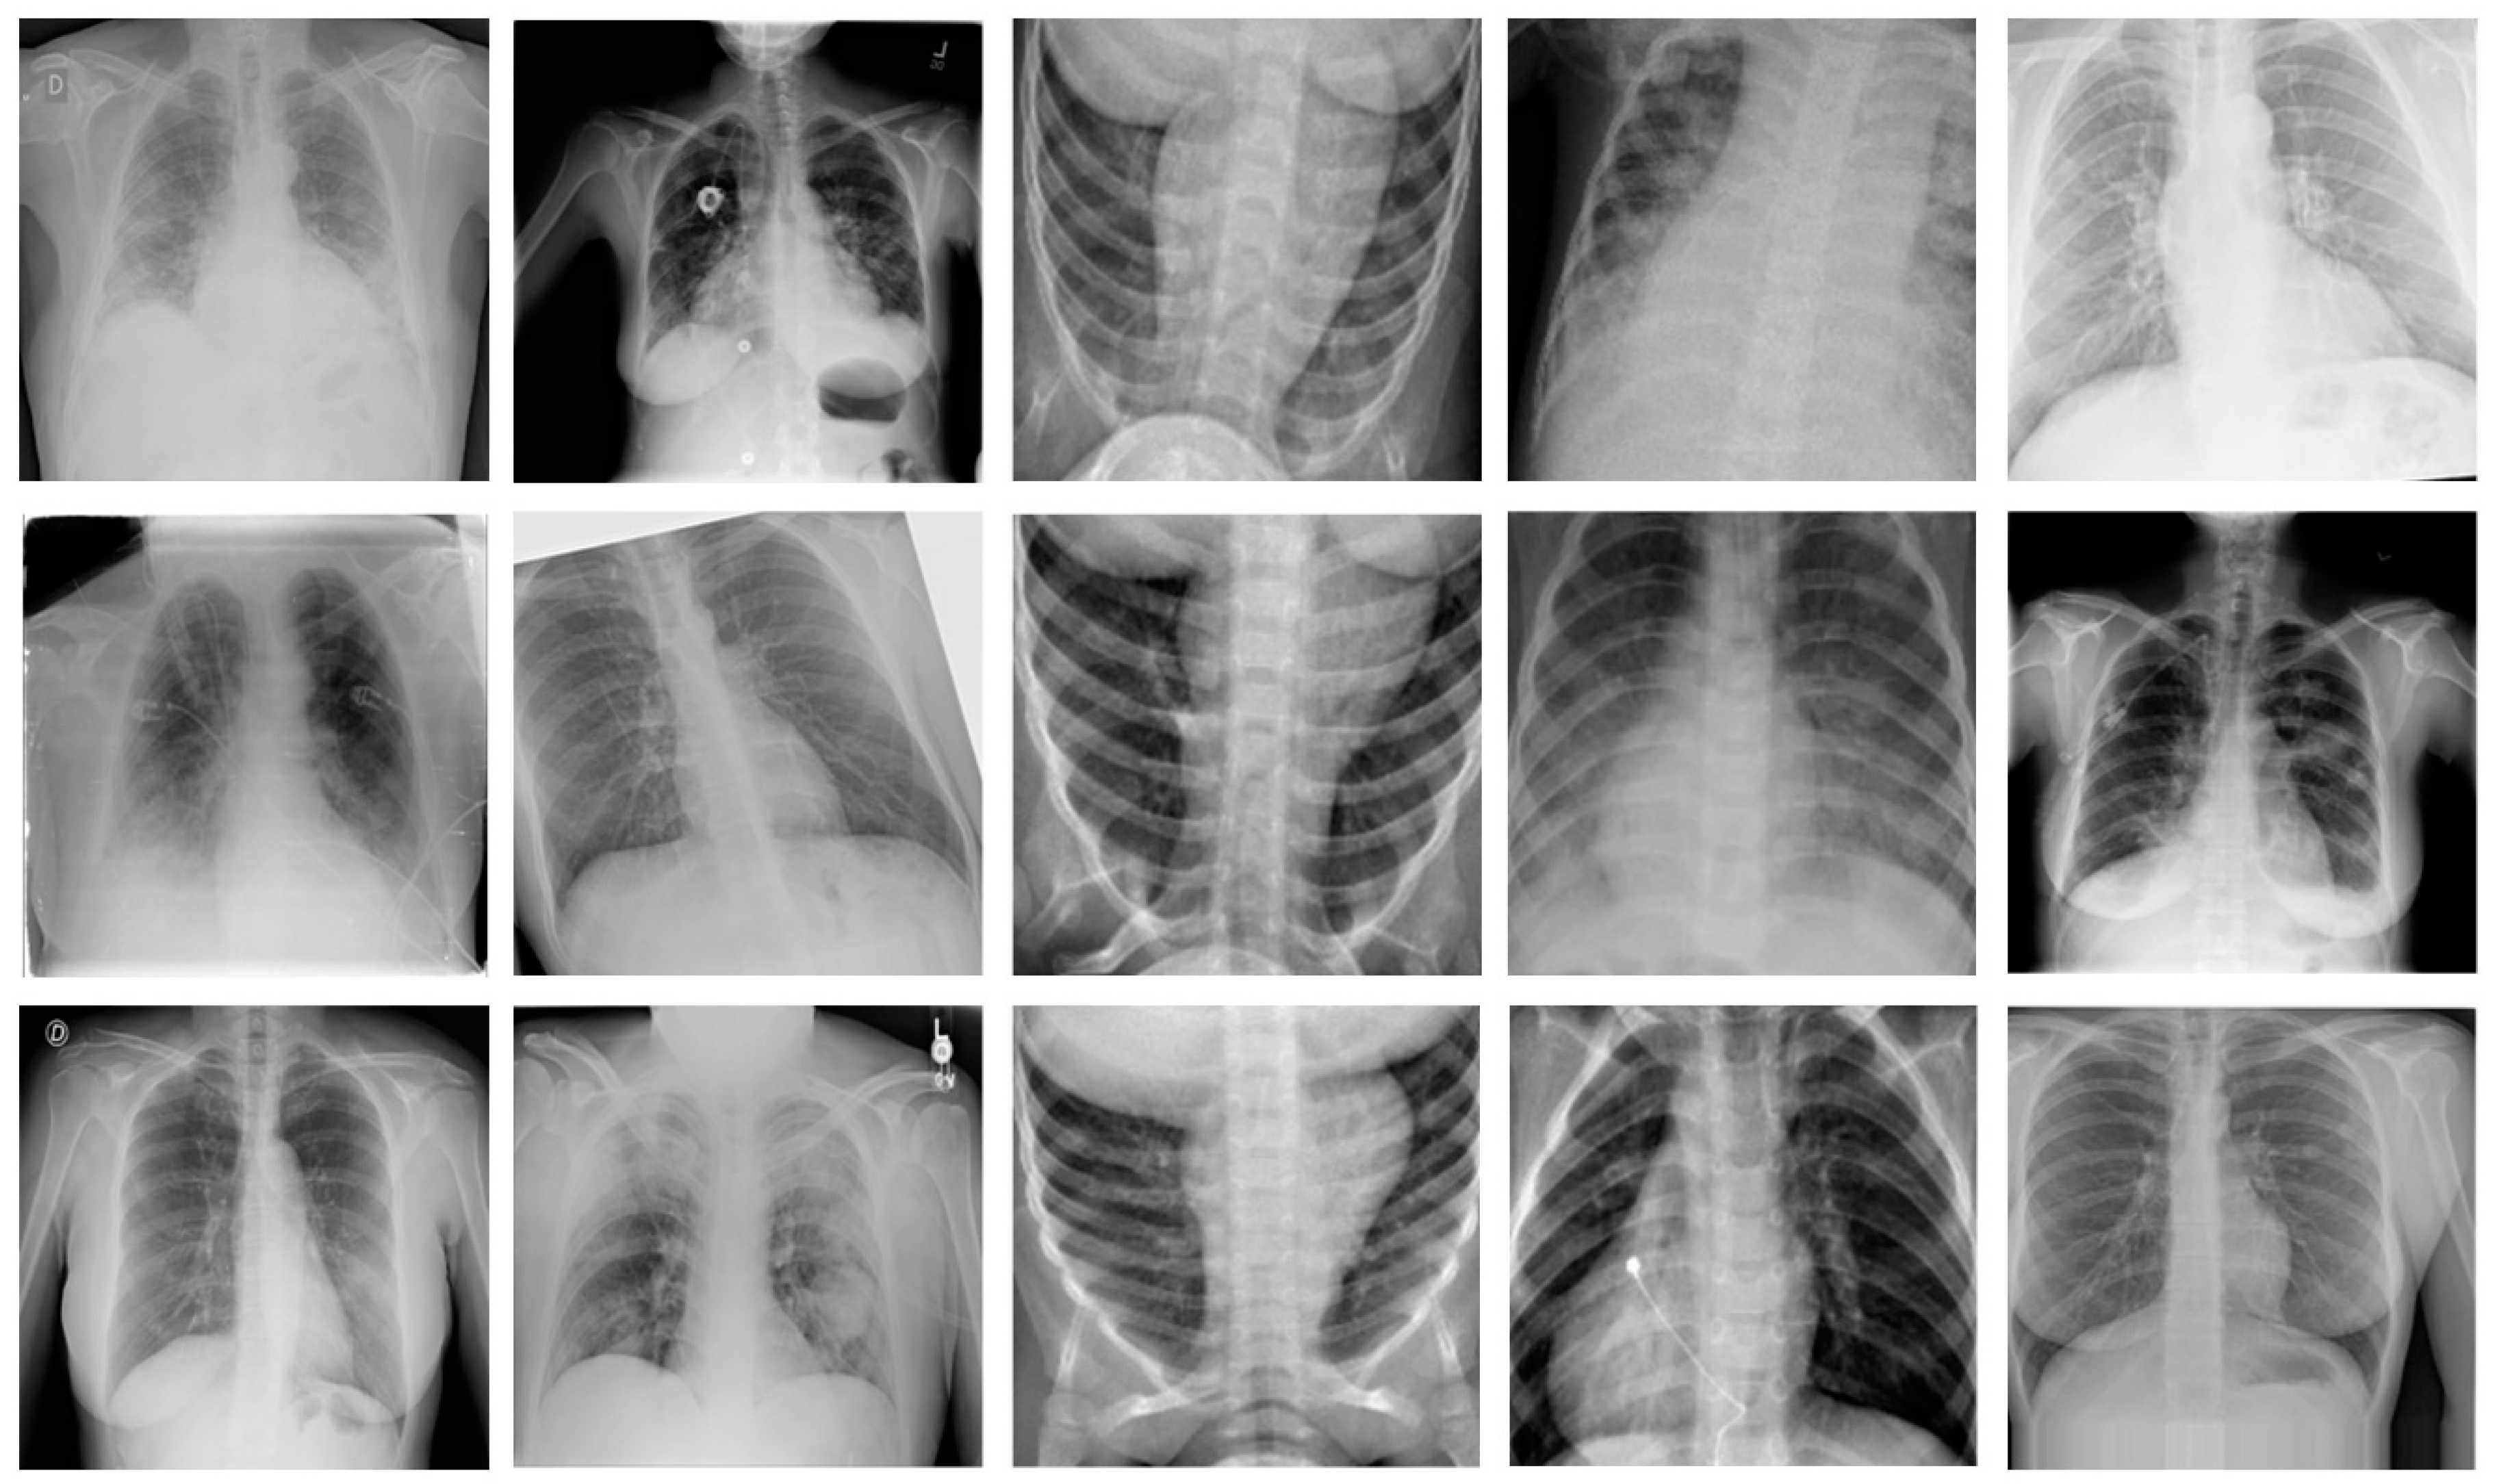

We have created another dataset by combining the CRIs from publicly available datasets with different lung diseases, i.e., VP, BP, COVID-19, normal, TB, and LO. As there does not exist any single dataset which can be used to classify the aforementioned lung diseases, we have combined the images of three publicly available datasets and used that integrated dataset to validate the performance of our framework. More specifically, we used COVID-19 and LO images from the “COVID-19 Chest Radiography database” dataset [37]. We applied augmentation on all images of the “Chest X-ray (COVID-19 & Pneumonia)” dataset [38] and used normal chest radiographs. Furthermore, we have used TB, BP, and VP CRIs of the “Lung Disease Dataset (4 types)” dataset [39]. The details of the dataset are provided in Table 4. Furthermore, Figure 2 shows some representative samples of dataset 2.